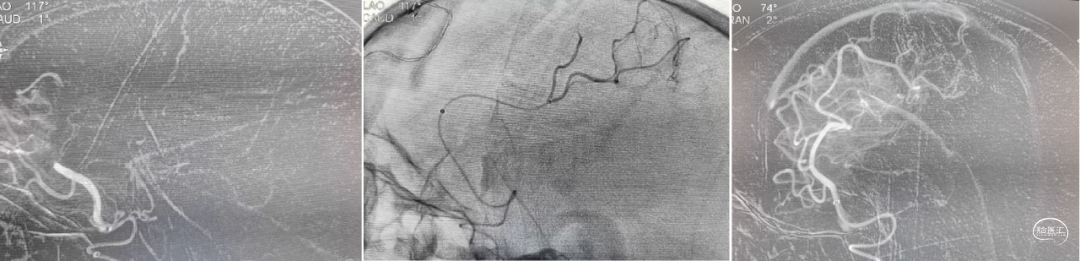

微导丝辅助微导管velocity到达左侧大脑前动脉A3段以远抽吸,利用微导管velocity持续抽吸后造影左侧大脑前动脉完全再通、前向血流Ⅲ级;最终双侧大脑前动脉血流恢复、前向血流Ⅲ级;左侧大脑中动脉下干远端栓塞部位血管细小迂曲故未干预、手术结束。

术后控制血压<140/90mmHg,第2天,患者神志清楚、言语恢复、左侧肢体肌力0级,NIHSS下降为8分,复查头部CT:左侧颞枕部局部梗死病灶;第4天,左侧肢体肌力4级,NIHSS2分。